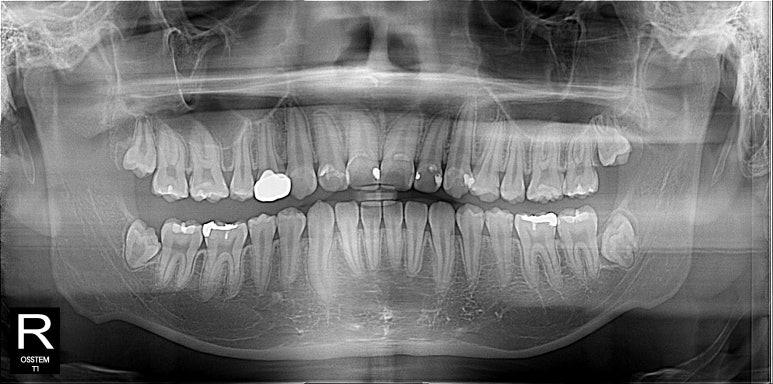

40대 고등학교 선생님, 최근 더 아래 앞니가 신경 쓰인다고..

전체 교정을 다해서 어금니 교합도 더 맞추고 앞니 수직수평피개까지 맞추면 더 좋지만 먹고 마시고 말하고 일상생활에 전혀 문제가 없는경우 불편한 부위만 해소해 주는 것이 좋다고 생각한다.

대략 8개월의 교정기간과 현재 5년간 잘 유지 중이다.